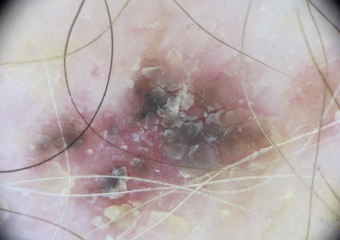

Actinic keratosis on posterior torso. Photo: International Skin Imaging Collaboration at isic-archive.com